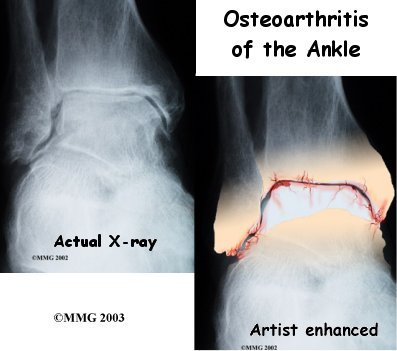

Your physician may take regular X-rays to see how severely the joint is damaged. This is usually the most important test to determine how bad the OA has become. How much articular cartilage is left in the ankle joint can also be estimated with the X-rays.

If there is any question whether the arthritis may be coming from something other than OA, blood tests may be ordered to look for systemic diseases such as rheumatoid arthritis. A needle may be inserted into the joint to remove some of the joint fluid. This fluid may be sent to a lab to look for crystals due to gouty arthritis or signs of infection.